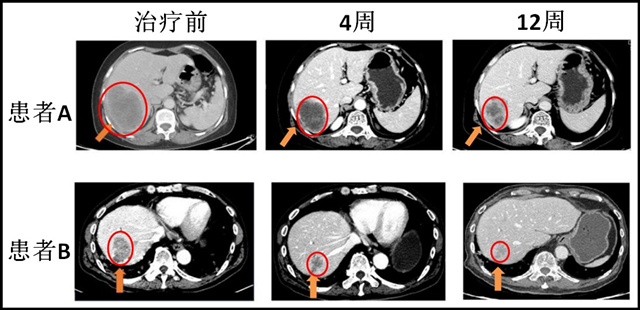

(患者使用艾维替尼AC0010治疗前后的对比)

两位患者肿瘤都明显缩小了30%以上。

这两位患者都是使用一代 EGFR 抑制剂大约2~4年以后,出现耐药性,基因检测确认有 T790M 突变。

1期临床中,30位 T790M 突变的患者,50%肿瘤缩小,40%肿瘤稳定,总疾病控制率是90%,效果良好。